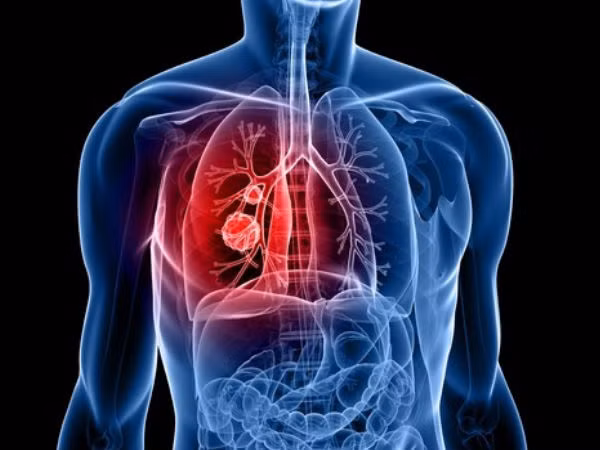

Theo đó, Dịch vụ Y tế Quốc gia Anh (NHS) kêu gọi những người có các triệu chứng như ho dai dẳng kéo dài hãy đi khám sớm, bởi theo các chuyên gia y tế, việc phát hiện bệnh sớm giúp ích cho quá trình điều trị bất cứ loại ung thư nào. Ảnh: Wikipedia.

Đặc biệt là bệnh ung thư phổi rất khó phát hiện trong giai đoạn đầu. Ảnh: SCC.